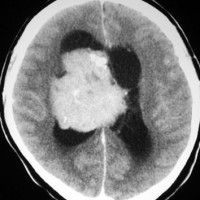

20代の男性の神経細胞腫です。側脳室の中のとても大きな腫瘍です。上段はガドリニウムという造影剤を入れた時のMRIです。下段の中央はCTですが,石灰化が見られます。脳外科の先生には,この脳室内腫瘍は一見transcallosal approach(経脳梁到達法)という手術で取れるように見えるかもしれませんが,そうではなくて,脳室の壁とくに上壁と側壁にくっついているのでなかなか取れません。この患者さんの場合は右の頭頂葉というところからtranscortical approach(経皮質到達法)で全摘出しました。後遺症もなく再発もなく術後10年が過ぎています。全部とれれば治ってしまう腫瘍です。

無症状で見つかった小さいcentral neurocytomaのCT像です